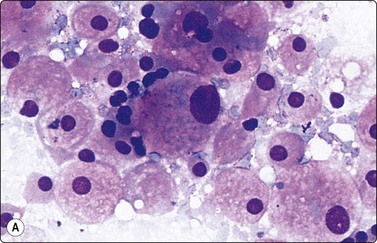

Smears from myelolipoma, adrenal and extra-adrenal, show a characteristic mixture of fat droplets, adipocytes and hematopoietic cells. The combination of these features in this site is diagnostic.119 Single megakaryocytes can be mistaken for pleomorphic malignant cells but are the hallmark of hematopoietic tissue in any site.